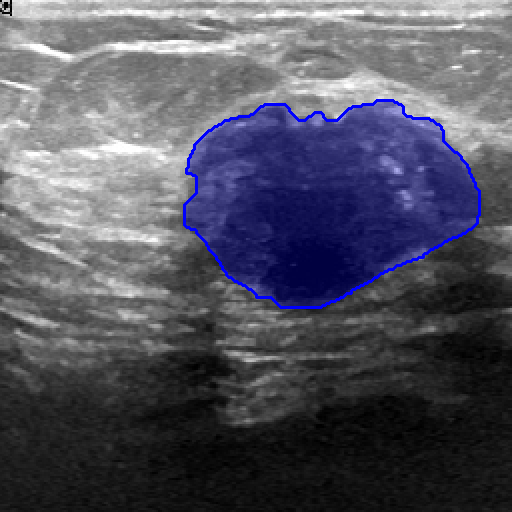

| Fine-Tuning | BUID [70] | 2D Ultrasound | 647 | Breast Cancer Segmentation | ||

| Method | ISIC-2018 (Skin Lesion) | JSRT (Lung X-ray) | KvaSir (Polyp) | Drive (Vessel) | BUID (Breast Cancer) | |

|---|---|---|---|---|---|---|

| Randomly (R50) | 86.16 0.14 | 93.10 0.12 | 62.85 1.32 | 59.82 2.00 | 65.54 0.21 | |

| Pre-trained ImageNet [60] | 86.87 0.47 | 94.52 2.66 | 83.85 1.32 | 65.12 1.55 | 72.64 1.14 | |

| Attention-Unet [77] | 86.81 0.51 | 94.47 2.71 | 82.23 1.41 | 65.02 1.44 | 72.19 1.16 | |

| U-Net ++ [78] | 86.71 0.49 | 94.32 2.81 | 82.23 1.41 | 65.38 0.78 | 73.76 2.83 | |

| 2D Supervised Method | Trans U-Net [76] | 86.60 0.82 | 89.80 0.35 | 67.11 0.24 | 62.63 0.24 | 67.90 0.40 |

| Twin-Barlon [13] | 86.01 0.07 | 94.56 3.09 | 83.00 0.23 | 65.73 1.46 | 74.46 1.19 | |

| Dino [79] | 86.79 0.09 | 94.84 2.79 | 79.84 1.62 | 65.39 0.81 | 76.21 0.57 | |

| SimCLR [15] | 87.28 0.21 | 94.79 2.93 | 82.20 0.51 | 65.22 2.18 | 76.52 0.22 | |

| Moco-v2 [17] | 87.24 0.14 | 94.05 3.52 | 78.24 1.35 | 64.92 2.21 | 75.93 1.96 | |

| Deepcluster-v2 [20] | 86.73 0.42 | 94.79 2.89 | 82.69 0.75 | 64.14 0.92 | 76.33 0.99 | |

| VicRegl [14] | 86.27 0.33 | 94.39 3.25 | 81.93 0.48 | 66.17 0.27 | 75.29 0.64 | |

| 2D-SSL on medical | LVM-Med (R50) | 87.76 0.30 | 95.13 2.64 | 86.76 0.94 | 66.97 0.27 | 78.65 0.72 |

| Clip [3] | 85.98 0.19 | 89.00 1.08 | 72.63 0.37 | 63.01 0.36 | 70.43 0.24 | |

| Flava [5] | 86.42 0.10 | 90.08 0.20 | 69.47 0.05 | 61.09 0.45 | 67.54 1.17 | |

| SAM [6] | 88.17 0.30 | 90.68 0.40 | 70.75 0.60 | 64.04 0.41 | 73.07 0.66 | |

| Foundation Model | LVM-Med (SAM’s ViT) | 88.41 0.28 | 90.74 0.47 | 73.10 0.08 | 65.49 0.12 | 77.20 0.42 |

| SAM (fixed encoder) [9] | 92.42 0.12 | 92.89 5.24 | 89.37 0.57 | 59.74 0.63 | 87.63 0.67 | |

| SAM with Prompt (no-train) [6] | 55.78 0.66 | 61.97 4.48 | 80.77 0.19 | 15.12 0.24 | 78.44 1.01 | |

| Prompt-based Seg. | LVM-Med (SAM’s ViT) | 92.48 0.07 | 93.74 4.06 | 90.09 0.14 | 63.01 0.02 | 89.69 0.61 |

In 3D settings, we segment 2D slices and merge results for a 3D volume. We also benchmarked with 3D self-supervised methods from [86]. Tables (2) and (3) show that our two versions with ResNet-50 and Sam’s ViT hold the best records in each category. For instance, we outperform 2D SSL methods trained on the same dataset, surpassing foundation models such as SAM, Flava, and Clip. In the prompt-based settings, LVM-Med also delivers better performance compared with SAM. Second, LVM-Med achieves the best overall results on seven of eight segmentation tasks, mostly held by LVM-Med with ResNet-50. The improvement gaps vary on each dataset, for e.g., from on Kvasir and BUID compared with 2D supervised methods.